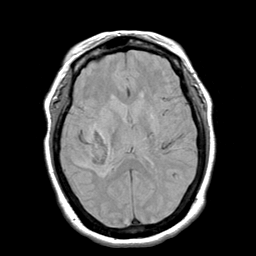

Cerebral hemorrhage, MR Study mr-pd -- Slice #13

[Home][Help][Clinical] Slice 13